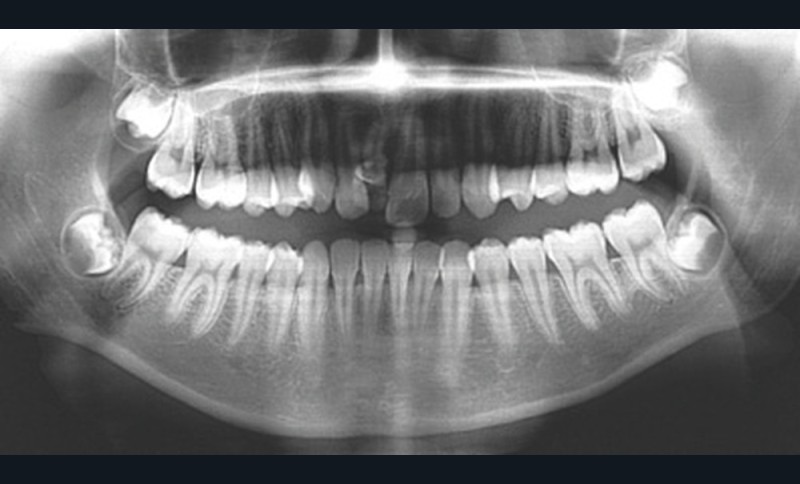

Son incisive centrale supérieure droite (11) présente un défaut de structure amélaire sévère, compromettant une technique restaurative pérenne a minima. L’examen de la panoramique (fig. 1e) et de la radiographie rétroalvéolaire de 11 (fig. 1f) objective une fracture coronaire verticale, ainsi qu’une racine grêle et courbe, peut-être en rapport avec un ancien traumatisme [1]. Le rapport couronne clinique/racine clinique est défavorable.

L’analyse de la téléradiographie de profil (fig. 1g) confirme une classe II squelettique à tendance hyperdivergente avec une normo-position de l’incisive mandibulaire dans sa symphyse. L’âge du patient et la croissance mandibulaire en rotation postérieure (travaux de Björk) ne permettront sans doute pas une correction de la classe II squelettique sans version de l’incisive mandibulaire.